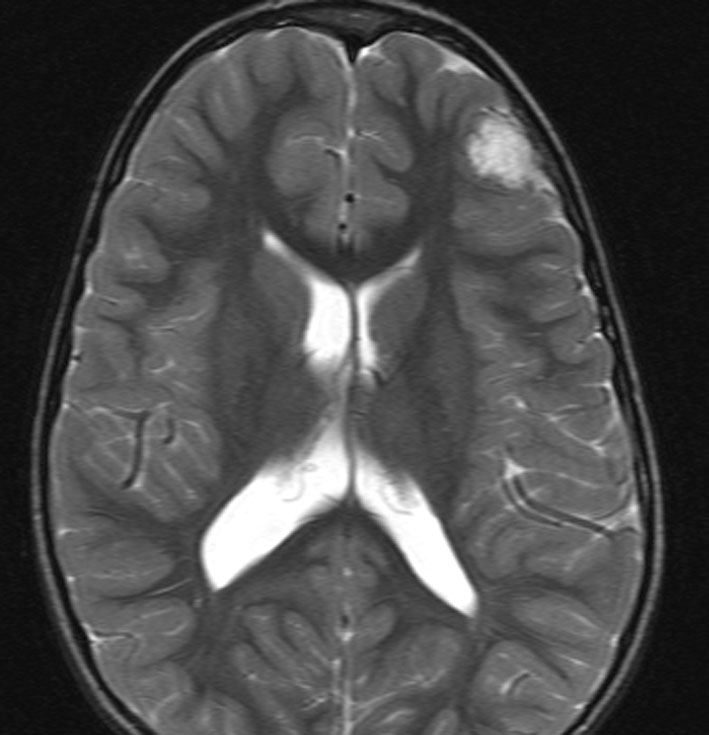

この患者さんは右前頭葉のびまん性星細胞腫に46グレイ23分割という低い線量の局所照射をしました。放射線治療8年後のMRI FLAIR画像です。腫瘍の再燃はなく,脳室周囲の白質が高信号になっています。脳梁や透明中隔の白質組織も高信号になり,非常に軽度の白質変性を示しています。でも,何の症状もありません。注意しなければならないのは,この所見を星細胞腫の再発あるいは進行と捉えて余分な治療をしないようにすることです。とくにグレード2の星細胞腫と乏突起膠腫の時に問題となります。